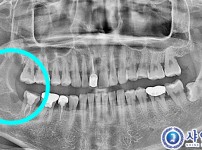

매복사랑니 발치 - 구강외과 전문의